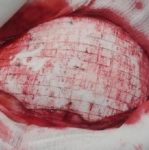

během operace

Operace trvala 3,5 hodiny. Implantace protézy Codubix® CT samotné trvala zhruba 30 minut.